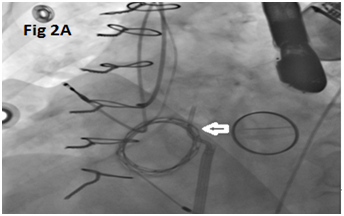

A 73-year-old female with mechanical mitral valve, tricuspid annuloplasty (32mm Edwards Physio Tricuspid incomplete ring) underwent Transcatheter Tricuspid Valve Replacement (TTVR) using off-label 29mm Edwards Sapien 3 (S3) Transcatheter Heart Valve (THV). Immediate post valve deployment, mild Perivalvular Leak (PVL) was noticed at the septal aspect (area of incomplete annuloplasty ring). Eighteen months later, patient presented with recurrent right heart failure and paracentesis due to severe tricuspid PVL (Figure 1A-C, Video 1). Percutaneous PVL closure under general anesthesia, Trans-esophageal Echocardiography (TEE) was performed. Via femoral venous access, defect was easily crossed with Agilis steerable sheath, multipurpose catheter and 0.035” glide wire. Despite recurrent attempts, wire came through the PVL but then traversed through open cells of S3 into the right ventricle (Figure 2A), confirmed with Armada 6mm balloon waist at the S3 cage (Figure 2B) (despite inflating 28mm Z med balloon inside S3 cage, Figure 2C). We decided to partially deploy the plug and assess valve function. Using 7.5F Asahi Eaucath multipurpose guide, a 12mm AmplatzerTM Vascular plug II (AVP II) was advanced through the defect. The ventricular disc was opened inside the S3 cage while body in the PVL defect (outside the S3 cage) and atrial disc on the atrial side of PVL (Figure 3A-B). With S3 function unaffected, no central leak and minimal gradient, PVL reduced to mild severity (Figure 4A-D, Video 2); the AVP II was successfully deployed (Figure 5). At 3-month follow up, there was an excellent symptomatic improvement (NYHA functional class I), with no heart failure re-hospitalization or paracentesis. Deployment of plug disc inside the valve frame is not recommended due to fear of interference with leaflet function and possible injury in long term. There was no immediate issue with the valve function in this case (due to space between the leaflet and frame of S3 and depends on size of plug used). Valve-in-Valve (S3-in-S3) would have certainly sealed all open cells treating this PVL but is more expensive option.

Figure 2 Multi-purpose diagnostic catheter (MPA) crossing through the PVL proximally and through the S3 cells distally (A), balloon inflation over a wire passed through the PVL channel confirms the position of hour-glass shaped inflated balloon with proximal half outside & distal half inside the S3 cage and waist in the middle (B), along with failed attempt to cross the MPA (white arrow in C) with Safari wire along with Zmed balloon inside the S3 (black arrow).